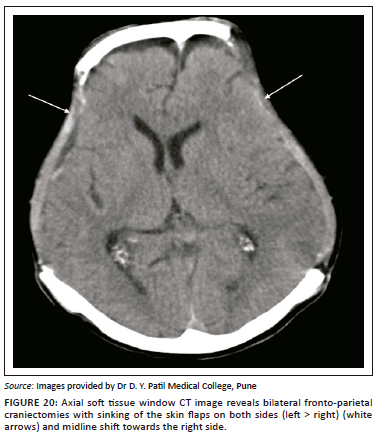

Paradoxical herniation

Paradoxical herniation is a rare, late complication in the post-craniectomy patient. It is characterised by a sunken skin flap and contralateral displacement and herniation of brain, with resultant mass effect, midline shift and effacement of CSF spaces (Figure 19 and Figure 20).20 The mechanism is usually a decrease in intracranial pressure because of lumbar puncture, ventricular drainage or ventriculoperitoneal shunting, which leads to an imbalance in the intracranial pressure and the atmospheric pressure. It is a potentially life-threatening condition, usually treated by clamping any shunts or drains, putting the patient in the Trendelenberg position, administering fluids and performing an early cranioplasty.22